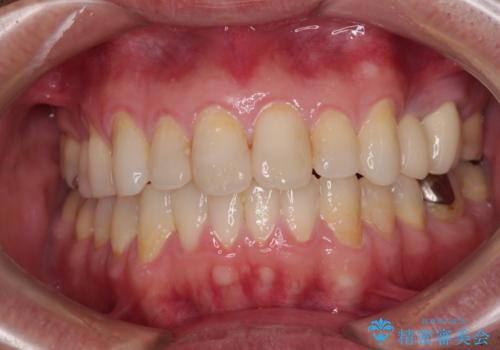

治療を長期化させたくないとのご要望があったので、左下の90度捻転した歯は、捻転した状態のゴールとしました。

反対咬合を改善したことで、歯ぎしりしたときの引っかかる感じがなくなり、奥歯への負担を大きく軽減することができました。